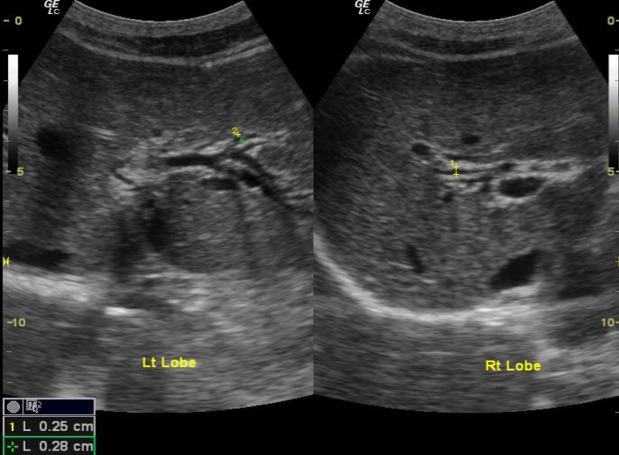

The study population was 4,337 villagers in Northern Thailand with a 5-year abdominal US surveillance. Patient demographics data and ultrasound findings of calcifications/granulomas, periductal fibrosis, and diffuse bile duct dilatation were included. A logistic regression model was used to determine significant predictors.

There were 4,225 people included with an average age of 45.49±7.66 years. Prevalence of calcifications/granulomas, periductal fibrosis, and diffuse bile duct dilatation detected on baseline sonographic surveillance was 11.7%, 20.5%, and 11.3%, respectively. The univariate analysis for significant predictors for CCA include age (Relative Risk; RR = 1.12), family history of CCA (RR = 2.29), periductal fibrosis (RR=2.38), and diffuse bile duct dilatation  (RR = 7.59). The multivariate analysis the independent predictors were age (RR = 1.12), family history of CCA (RR = 1.92), and diffuse bile duct dilatation (RR = 5.94), respectively.

The sonographic predictor for CCA surveillance in endemic areas is diffuse bile duct dilatation.  Age and family history of CCA are also helpful clinical markers.